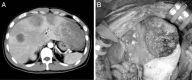

The rupture of a metastatic mixed adenoneuroendocrine carcinoma (MANEC) has not been previously reported, although the neuroendocrine cell carcinoma is often associated with a high incidence of hepatic metastases. The patient was a 39-year-old male who presented with upper abdominal pain over 3 months. Computed tomography showed multiple tumors in both hepatic lobes, while lower gastrointestinal endoscopy revealed a tumor in the transverse colon. Histopathologic examination of the tumor revealed it to be a neuroendocrine cell carcinoma. After the resection of the primary tumor, hepatic metastases rapidly increased, and one of them in the left lateral segment was ruptured with significant hemorrhage. The rupture led us to undertake the emergency operation to stop the bleeding. Histology showed a high-grade large-cell neuroendocrine carcinoma associated with moderately differentiated tubular adenocarcinoma. The Ki-67 labeling index was 80% (G3). The diagnosis was mixed adenoneuroendocrine carcinoma according to the 2010 World Health Organization guidelines. Hepatic arterial infusion chemotherapy, systemic chemotherapy, and transcatheter arterial chemoembolization did not decrease the tumor progress, and the patient died on postoperative day 110. Reporting this highly malignant case, I hope all doctors can be interested in MANEC.